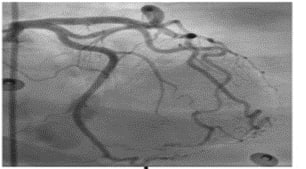

1 Acute coronary syndrome with

ST-segment elevation and coronary

syndrome without ST-segment elevation

2 Acute myocardial injury without vascular atherosclerosis